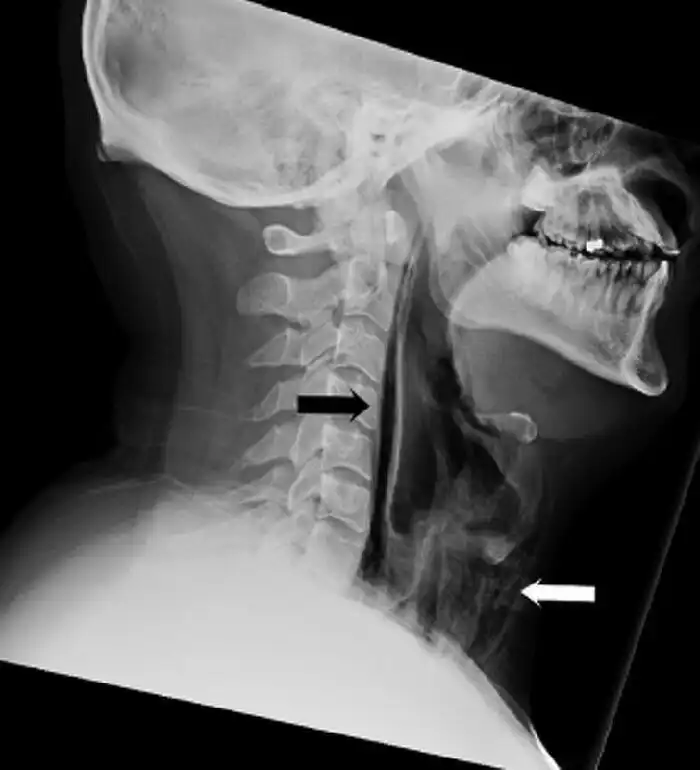

Вот что случается, если попробовать чихнуть с закрытым ртом и носом. Глотка не выдерживает давления, и образовывается рана